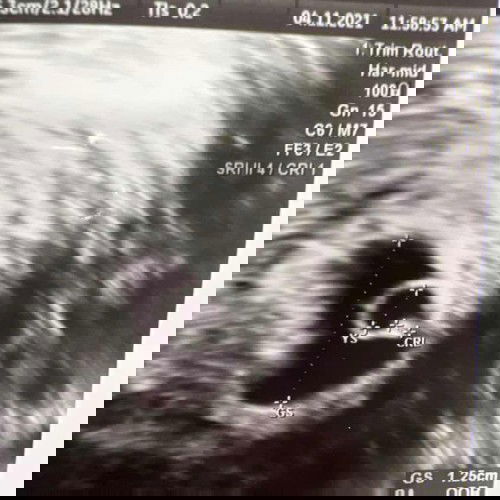

ช่วยดูหน่อยค่ะแม่ๆ

ไปอัลตร้าซาวน์มาค่ะ คุณหมอบอกว่าประมาณ 5 วีค ถือว่าเล็กไปไหมคะ นัดอีกทีอาทิตย์หน้าค่ะ ตอนนี้ค่อยข้างกลุ้มใจมาก เพราะเห็นถุงตั้งครรภ์ เห็นถุงไข่แดง เห็นตัวเบบี๋ แต่ยังไม่สามารถฟังเสียงหัวใจได้ค่ะ อยากขอความคิดเห็นจากแม่ๆทุกคน ท้องแรกกังวลไปหมดเลยค่ะ 😔😔

ของเราอัลตร้าซาวด์ 5wก็ไม่ได้ยินเสียงหัวใจค่ะตอน 7wถึงจะได้ยิน